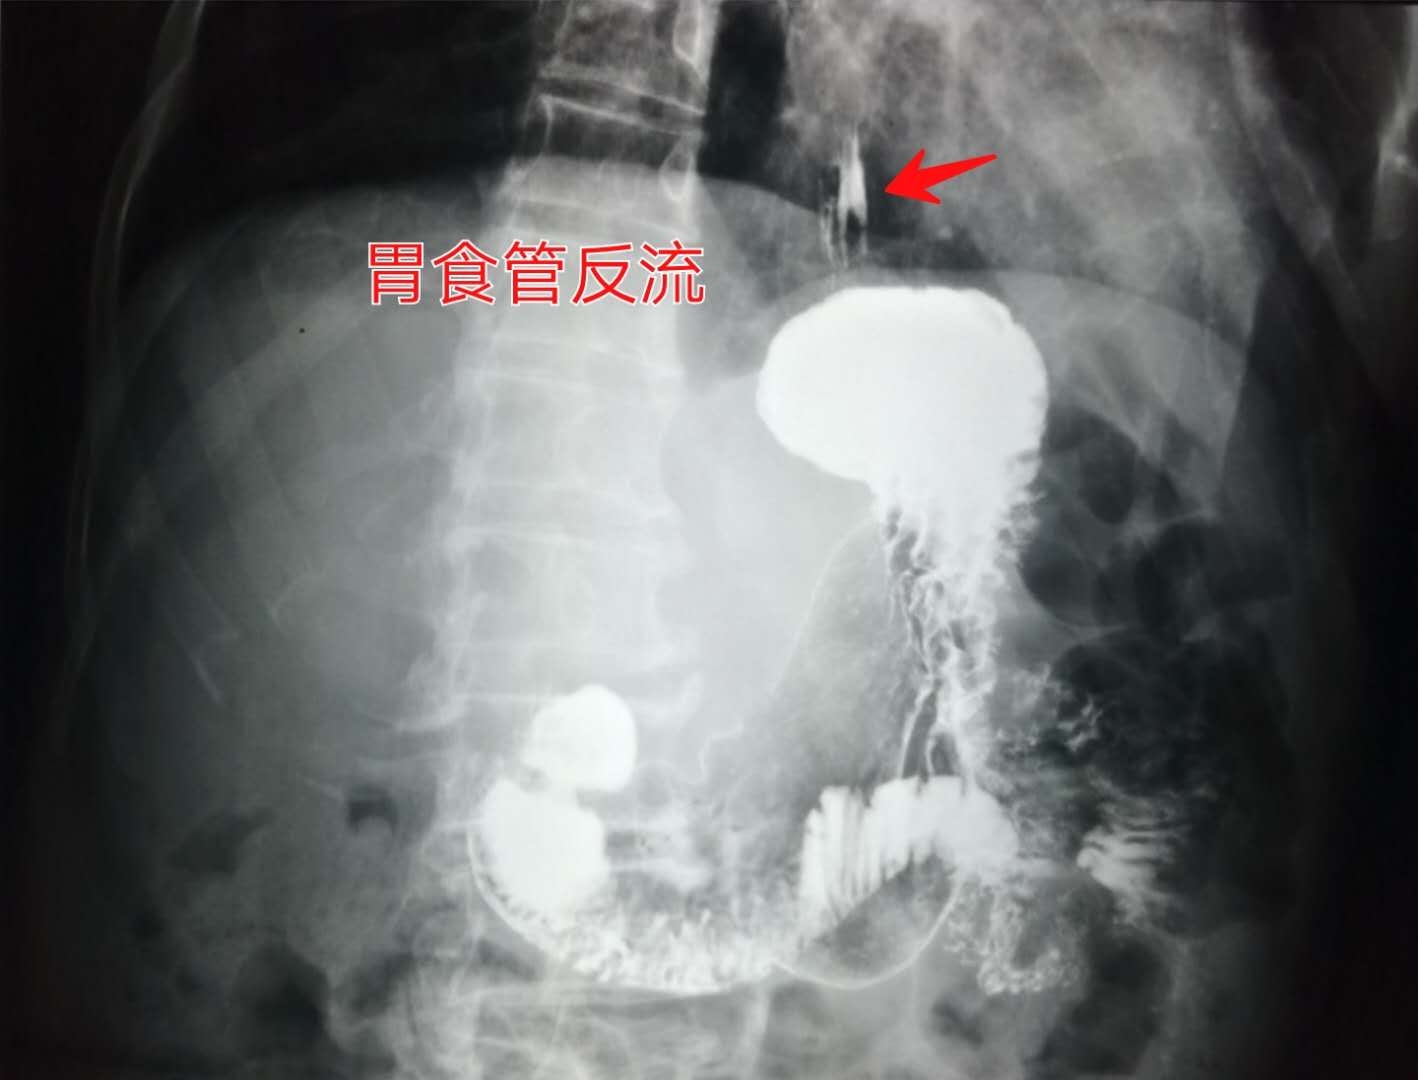

常用的方法是胃食管双对比造影(钡餐检查)。

早期表现为食管下段轻微痉挛性改变,食管粘膜局部增粗;进一步发展可见食管壁毛糙,出现针尖状或星芒状小溃疡。

像下图这位65岁的老爷子,喝下钡餐后,仰卧位观察,白色的硫酸钡从胃内反流进入食管,同时观察到食管粘膜增粗,是比较典型的反流性食管炎: